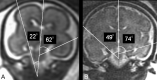

Fig 1.

The method used to assess the hippocampal infolding angle (HIA) is shown on the coronal T2-weighted single-shot, fast spin-echo section encompassing the pons.